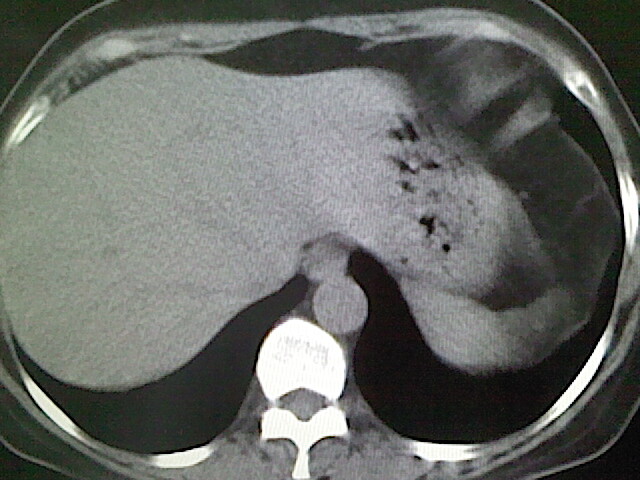

女,52岁,咳嗽,咳痰多日

左下肺陈旧纤维索条!

左肺舌段炎性改变

我见过几例,为炎症后纤维条索

慢性炎症后改变

考虑慢性炎性病灶粘连牵拉改变。

左肺舌叶纤维锁条病变。

左肺上叶下舌段炎症并局部胸膜反应。

左肺舌叶纤维索条影。

左肺舌叶段陈旧性病变

左肺舌段炎性反应。片子的质量太不好了。

左肺舌段炎性

炎性改变

左肺舌叶纤维索条影